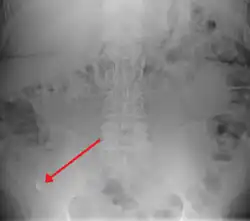

![]() | |

| A fecalith marked by the arrow which has resulted in acute appendicitis. | |

-

Appendicolith as seen on plain X ray